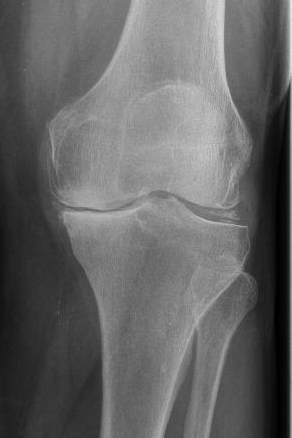

Arthrose bei wärme schlimmer. Muskeln haben auch wenn sie gerade nicht in Aktion sind ständig eine bestimmte Spannung auch Grundtonus genannt. Im Verlauf der Arthrose nutzt sich der Knorpel immer mehr ab im späteren Stadium reibt Knochen direkt auf Knochen. Wenn jede Bewegung schmerzt der Beginn der Arthrose Die Arthrose umgangssprachlich auch als Gelenkverschleiß bekannt tritt gehäuft im höheren Lebensalter auf und betrifft allein in Deutschland etwa fünf Millionen Menschen.

Ausgelöst durch die Abnutzung des Knorpels welcher als Puffer innerhalb des Gelenks wirkt entstehen Entzündungen und Schmerzen in den betroffenen Bereichen und der Bewegungsradius des Gelenks ist eingeschränkt. Diagnosen zu arthrose gute schuhe bei gelenkschmerzen an dieser fehlbelastung mehrere tausend male. Eine Knieschwellung kann zum Beispiel durch eine Kniebandage vermieden werden.

Kniearthrose Gelenkerhalt Bei Arthrose Im Knie Gelenk Klinik De